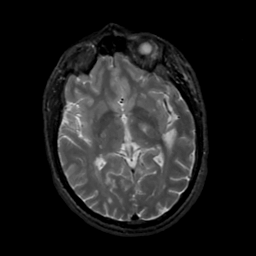

MR Study #5, March 10, 1991 -- Slice #26